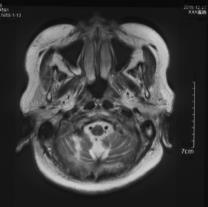

复阅2018年12月27日MRI片:左侧额颞部颅骨修补术后改变,两侧额颞叶、右侧小脑半球、左侧侧脑室后角旁均见长T1长T2异常信号,脑室系统扩大。提示左侧额颞部颅骨修补术后,两侧额颞叶、右侧小脑半球、左侧侧脑室后角旁软化灶形成。

图7-12,2018年12月27日MRI片,左侧额颞部颅骨修补术后,两侧额颞叶、右侧小脑半球、左侧侧脑室后角旁软化灶形成